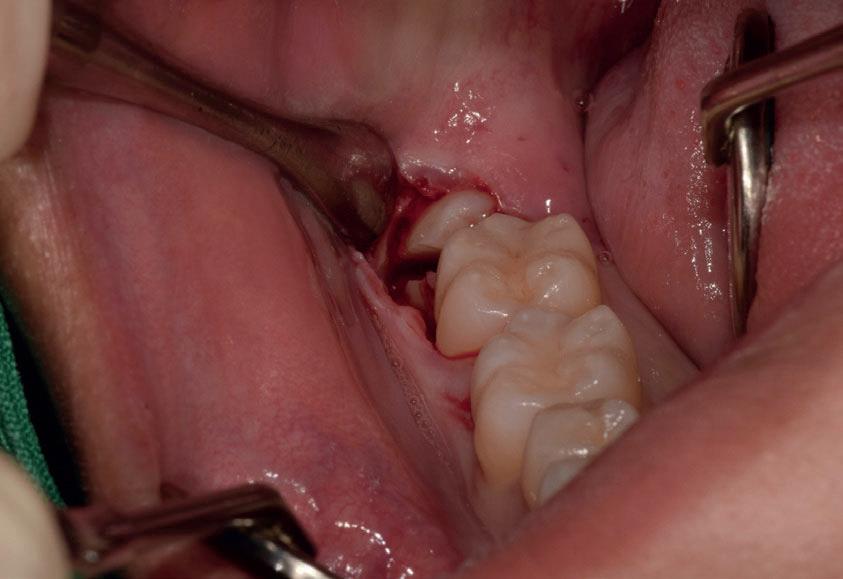

Il seguente caso chirurgico è di un 4.8 mesio-inclinato e parzialmente incluso. Dopo un’incisione a busta, il

dente è stato separato al centro per fare una coronectomia, prima della porzione distale e successivamente della porzione mesiale. Facendo leva quindi è stato possibile rimuovere le radici unite. Figg. 165-172

Figg. 165-172 - Caso 3: tecnica di estrazione con divisione orizzontale utilizzando il manipolo dritto. Fig. 165 Fig. 166 Fig. 167 Fig. 168 Fig. 169 Fig. 170 Fig. 171 Fig. 172